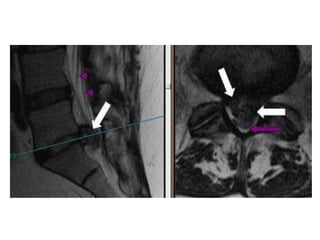

Case based discussions:  68 year old female, Hypertensive and Diabetic. Diabetes is poorly controlled. She presented with 6 months of progressive numbness in the hands and feet. Glove and stocking distribution. There are no other symptoms. Clinically, she has no motor deficits in all 4 limbs but has hyper reflexia. Objective sensory change was mostly in C7/C8 dermatomes bilaterally. Bowel and bladder function and walking were satisfactory.

MRI SCAN SAGITTAL T2W

Surgery performed was an anterior cervical discectomy and fusion using the patients’ iliac bone.  I decided to fuse at two levels C4/C5 and C5/C6 though the main focus was really to do a good decompression of the space behind the C5/C6 disc, which is the site of maximal compression on the MRI scan.

Lumbar MRI (sagittal view)

Lumbar MRI (axial view)

Surgery performed wasan anterior cervical discectomy and fusion using the patients’ iliac bone. I decided to fuse at two levels C4/C5 and C5/C6 though the main focus was really to do a good decompression of the space behind the C5/C6 disc, which is the site of maximal compression on the MRI scan.